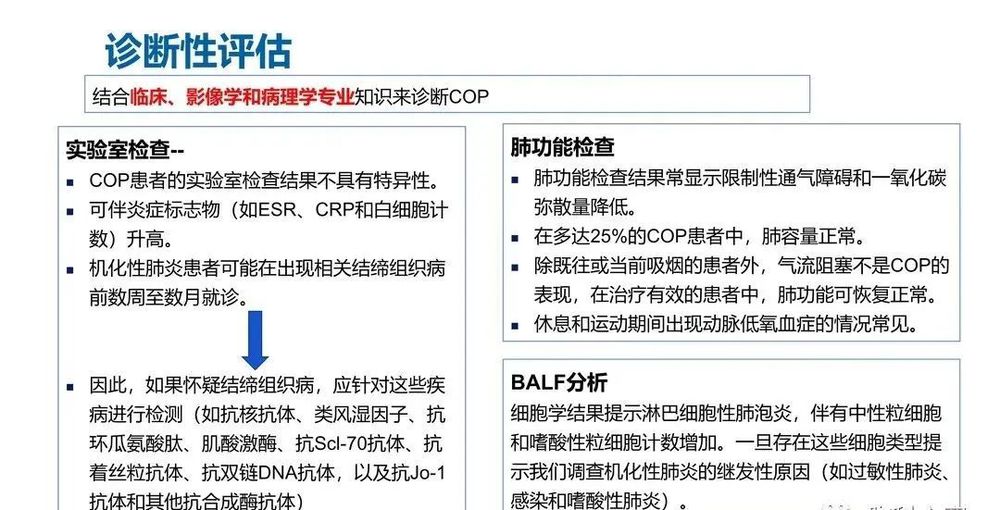

实验室检查缺乏特异性,肺泡灌洗液(BALF)中细胞成分的变化对COP的诊断有一定的预测价值。除了BALF外,其他实验室辅助检查对COP的诊断帮助不大。由于临床表现缺乏特异性,COP诊断常常被延误。

COP诊断必须在获得机化性肺炎病理诊断的基础上,结合临床、影像及其他辅助检查资料进行综合分析,排除可能导致机化性肺炎的其他疾病后,方能考虑为本病。目前,COP的诊断主要依据临床和肺CT表现,甚至单纯依靠CT影响特征,COP诊断的准确性可达90%。